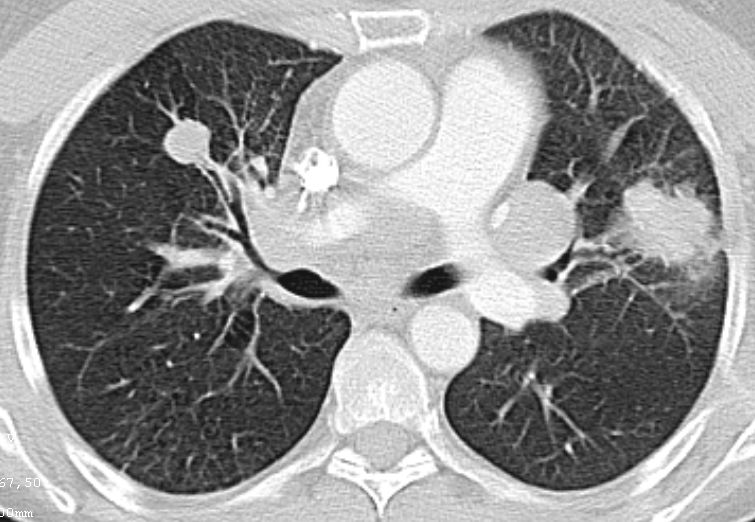

| Lungenmetastasen | 53-jährige Frau mit einem primär zerebral und pulmonal metastasierten Adenokarzinom des linken Oberlappens cT4 cN1 M1.

Das CT zeigt den Primärtumor links und einen Rundherd rechts (möglicherweise 2. Primärtumor).![]() | |||